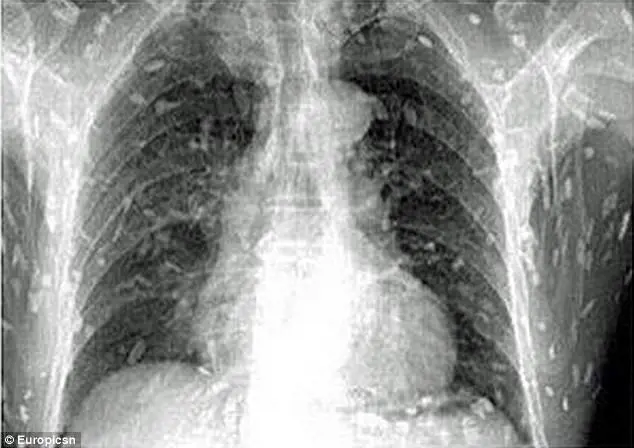

A quanto pare è stato il pesce crudo mangiato al ristorante a causare tutti i problemi al protagonista di questa disavventura. Una volta mangiate le prelibatezze giapponesi, il corpo di quest'uomo cinese è stato invaso da vermi solitari ed è stato immediatamente ricoverato al Guangzhou No. 8 People's Hospital nella provincia cinese di Guangdong. Le uova della tenia possono causare la cisticercosi, quando i vermi adulti penetrano nel sangue umano